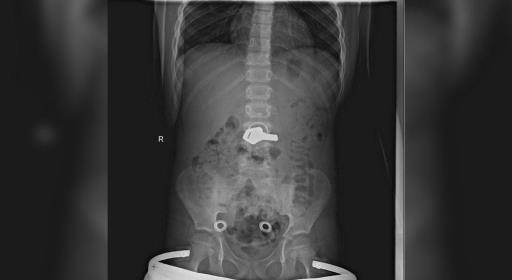

Московские врачи достали из желудка ребёнка связку ключей

Родителей призывают внимательнее следить за своими чадами и не откладывать обращение к медикам в случае необходимости. Читать далее...